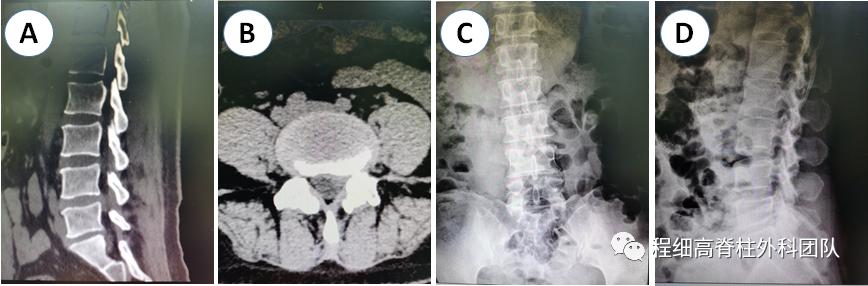

图2 术前CT未见明显骨化,DR提示L4/5椎板间隙较窄